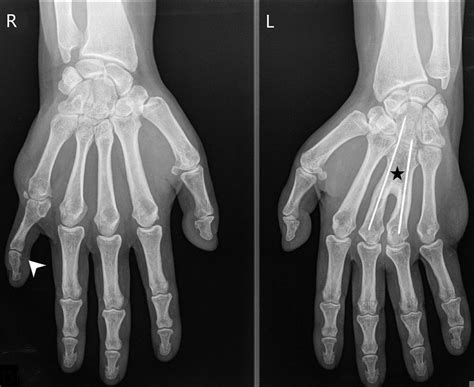

• Clinical evaluation: A thorough physical examination and medical history can help identify characteristic features of Pallister W Syndrome. This may include assessing facial features, skeletal abnormalities, and other physical signs.

• Imaging studies: Imaging studies such as X-rays, CT scans, and MRI scans can help identify structural abnormalities in the brain, heart, and other organs. These studies can provide valuable information about the extent and severity of the condition.